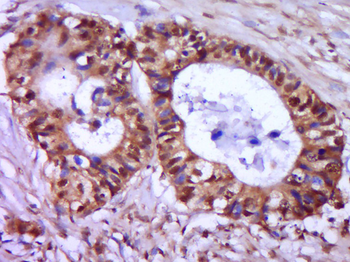

CDKN1A Antibody

Catalog Number: orb682382

| Description | CDKN1A Antibody |

| Target | CDKN1A |

200 μl, 50 μl, 100 μlCDKN1A/p21 Rabbit Polyclonal Antibody [orb11203]

FC, ICC, IF, IHC-Fr, IHC-P

Bovine, Canine, Gallus

Human, Mouse, Rat

Rabbit

Polyclonal

Unconjugated

50 μl, 100 μl, 200 μlPhospho-PAK6 (Ser560) Rabbit Polyclonal Antibody [orb6634]